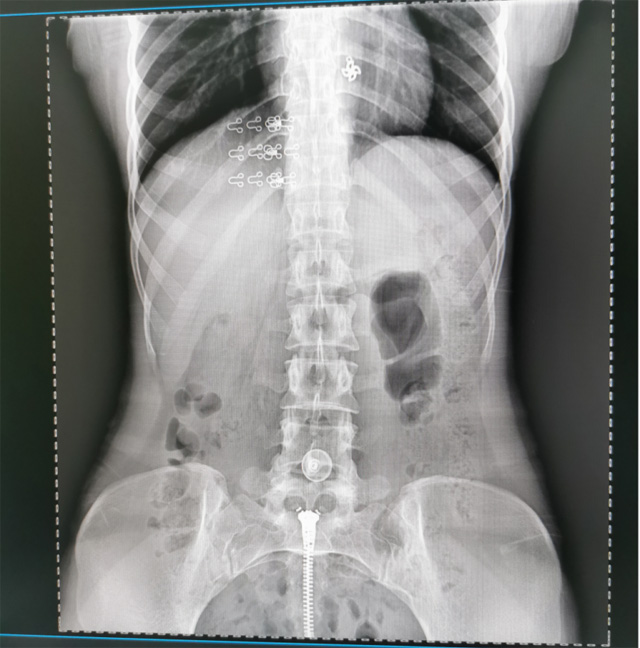

提高醫(yī)院的影像科的醫(yī)療服務(wù)水平,滿足滿足人民群眾不斷增長的醫(yī)療需求,促進(jìn)醫(yī)療技術(shù)快速發(fā)展。醫(yī)院都引進(jìn)懸吊DR拍片設(shè)備新一代數(shù)字化X線攝影系統(tǒng)。標(biāo)志著醫(yī)院的診療水平又上升一個新的臺階。懸吊DR滿足人體頭部、胸部、腹部、腰椎、四肢等部位的數(shù)字?jǐn)z影檢查,可以檢查呼吸系統(tǒng)疾病,心臟系統(tǒng)的疾病、骨關(guān)節(jié)系統(tǒng)的疾病,子宮輸卵管造影、胃腸道造影,.有職業(yè)病體檢篩查塵肺病功能。通過DR數(shù)字化攝影,分段連續(xù)、重疊采集數(shù)字化圖像,利用軟件對圖像進(jìn)行拼接的方式來獲得全脊柱、全上肢或全下肢的圖像。新設(shè)備的圖像更清晰,臨床拍攝避免患者再次搬運(yùn)和移動產(chǎn)生的痛苦,是創(chuàng)傷骨折患者的福音。輻射減少受照劑量50%,后處理能力強(qiáng)、圖像質(zhì)量高。有效降低操作難度,縮短工作流程,尤其適合大批量體檢。

具有射線劑量小、圖像清晰度高、誤差小等特點(diǎn),懸吊DR已廣泛應(yīng)用于各級醫(yī)療機(jī)構(gòu)的體檢中心,越來越受到臨床醫(yī)生的肯定和患者的青睞。為臨床診斷工作提供更加直觀有效的技術(shù)支持,大大提高了患者就醫(yī)效率從而為患者提供更加優(yōu)質(zhì)的醫(yī)療服務(wù)。提高了其成像質(zhì)量和臨床應(yīng)用價值,并極大減少了受照輻射劑量。有效滿足了各種常見疾病的臨床診斷和治療需求。以醫(yī)療質(zhì)量為根本,以優(yōu)質(zhì)服務(wù)為導(dǎo)向,竭誠為人民群眾的健康保駕護(hù)航。